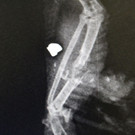

Brieftaube_Projektil.jpg

Download Photo (1024 x 683)

Wiener+Tierschutzverein

Datum: 20.09.2017

Betrachtungen: 1